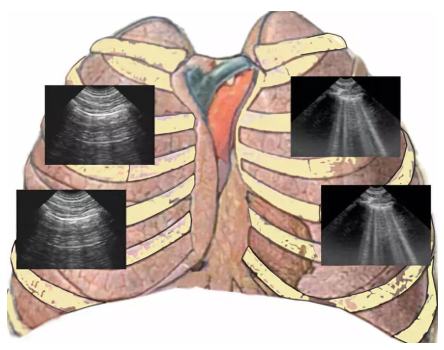

无论在急诊室,还是普通病房,呼吸困难患者非常常见。一般情况下,医生通过询问病史和查体对引起呼吸困难的病因进行初步判断:究竟是心源性呼吸困难(急性失代偿性心力衰竭等),还是肺源 性呼吸困难(慢阻肺、哮喘、特发性肺间质纤维化等),或是其他疾病引起的呼吸困难(严重贫血、脑出血、脑外伤、大量腹水、腹腔内巨大肿瘤、甲亢危象等)。与此同时,我们能想到的辅助检查包括胸部X线片、心脏彩超、采血查BNP或心肌标志物等,这些当然是可取的,但等待结果需要一定的时间。对于急危重症患者而言,病情进展迅速,死亡风险高,迫切需要在短时间内做出准确判断并给予针对性的治疗。但对于部分临床医生,尤其是年轻医生而言,仅凭经验判断可能会贻误病情。因此,寻找简单、快捷、准确的鉴别方法十分必要。而超声具有无创、实时、动态、可重复的优点,成为了临床医生的选择。肺部超声扫描方案有多种,例如八分区法、十二分区法、俯卧位十六分区法、BLUE方案、BLUE Plus方案等。对于急性呼吸困难患者,建议选择BLUE方案进行快速筛查。研究证实,BLUE方案对气胸的敏感性为88%,特异性为100%,对于肺炎的敏感性和特异性也能达到90%左右[1]。BLUE方案扫描的四个点分别是上蓝点、下蓝点、膈肌点和PLAPS点(图1),通过这四个点的扫查来快速排除危及生命的情况。(1)首先检查胸膜滑动征,如果双侧前胸壁胸膜滑动征存在,且双肺以B线为主(B profile),可判定存在肺水肿。导致肺水肿的原因有很多,主要有肺部疾病,如间质性肺炎、病毒性肺炎、真菌性肺炎、肺间质纤维化、ARDS以及心脏疾病引起的心源性肺水肿等。临床上如果观察到上述征象,应注意进一步观察胸膜线的形态,如果胸膜线增粗、增厚、不连续、不光滑,此时就应考虑肺部疾病的可能性较大。ARDS是各种原因引起的肺泡上皮细胞和肺毛细血管内皮细胞损伤,从而引起弥漫性肺泡损伤。由于ARDS患者肺动脉压和肺血管静水压增高,肺血管通透性高,导致进入肺间质和肺泡的液体和蛋白质增多,从而出现肺容积减少、通气血流比例失调、通气不均衡、肺顺应性下降。肺部超声则可见胸膜线粗糙、增厚、不规则;B线分布不均匀,所有肺野中至少有一个肋间隙不会出现B线,但随着重力的改变,B线数量会逐渐增多、融合。前胸壁胸膜线下一般可见肺部局灶炎变征象;随着重力改变,在重力依赖区,也就是我们的侧胸壁、PLAPS点,可见炎变范围逐渐扩大,部分ARDS患者可以出现肺不张征象;胸膜滑动征从前胸壁至侧胸壁至背部,依次表现为正常至减弱甚至消失,这是典型的ARDS超声改变。由此可见,我们不能单纯通过一个区域来判定患者的病情,而是要综合患者病史及多个区域的肺超改变进行判定。如果胸膜线光滑、清晰、锐利,同时B线也是双肺弥漫且均匀分布,此种情况要考虑流体力学性肺水肿。流体力学性肺水肿(包括心源性、容量过负荷性)的产生是以肺毛细血管静水压升高作为主要驱动因素。当舒张功能减弱,左房压升高时,各级肺小血管承受的压力近等,因此引发的肺水肿在分布区域和程度上大致相同。此时建议进一步完善心脏及下腔静脉的超声检查,如超声心动图提示心脏收缩功能降低、左房压增高或存在左心和右心运动不匹配等征象,且下腔静脉充盈、固定,变异度较低时则考虑心源性肺水肿。如果超声心动图无异常,但下腔静脉充盈、固定,则可结合患者临床表现、中心静脉压以判定存在容量过负荷所致肺水肿的可能。(2)如果双侧前胸壁胸膜滑动征存在,且可以看到A线,此种情况称为“A profile”。